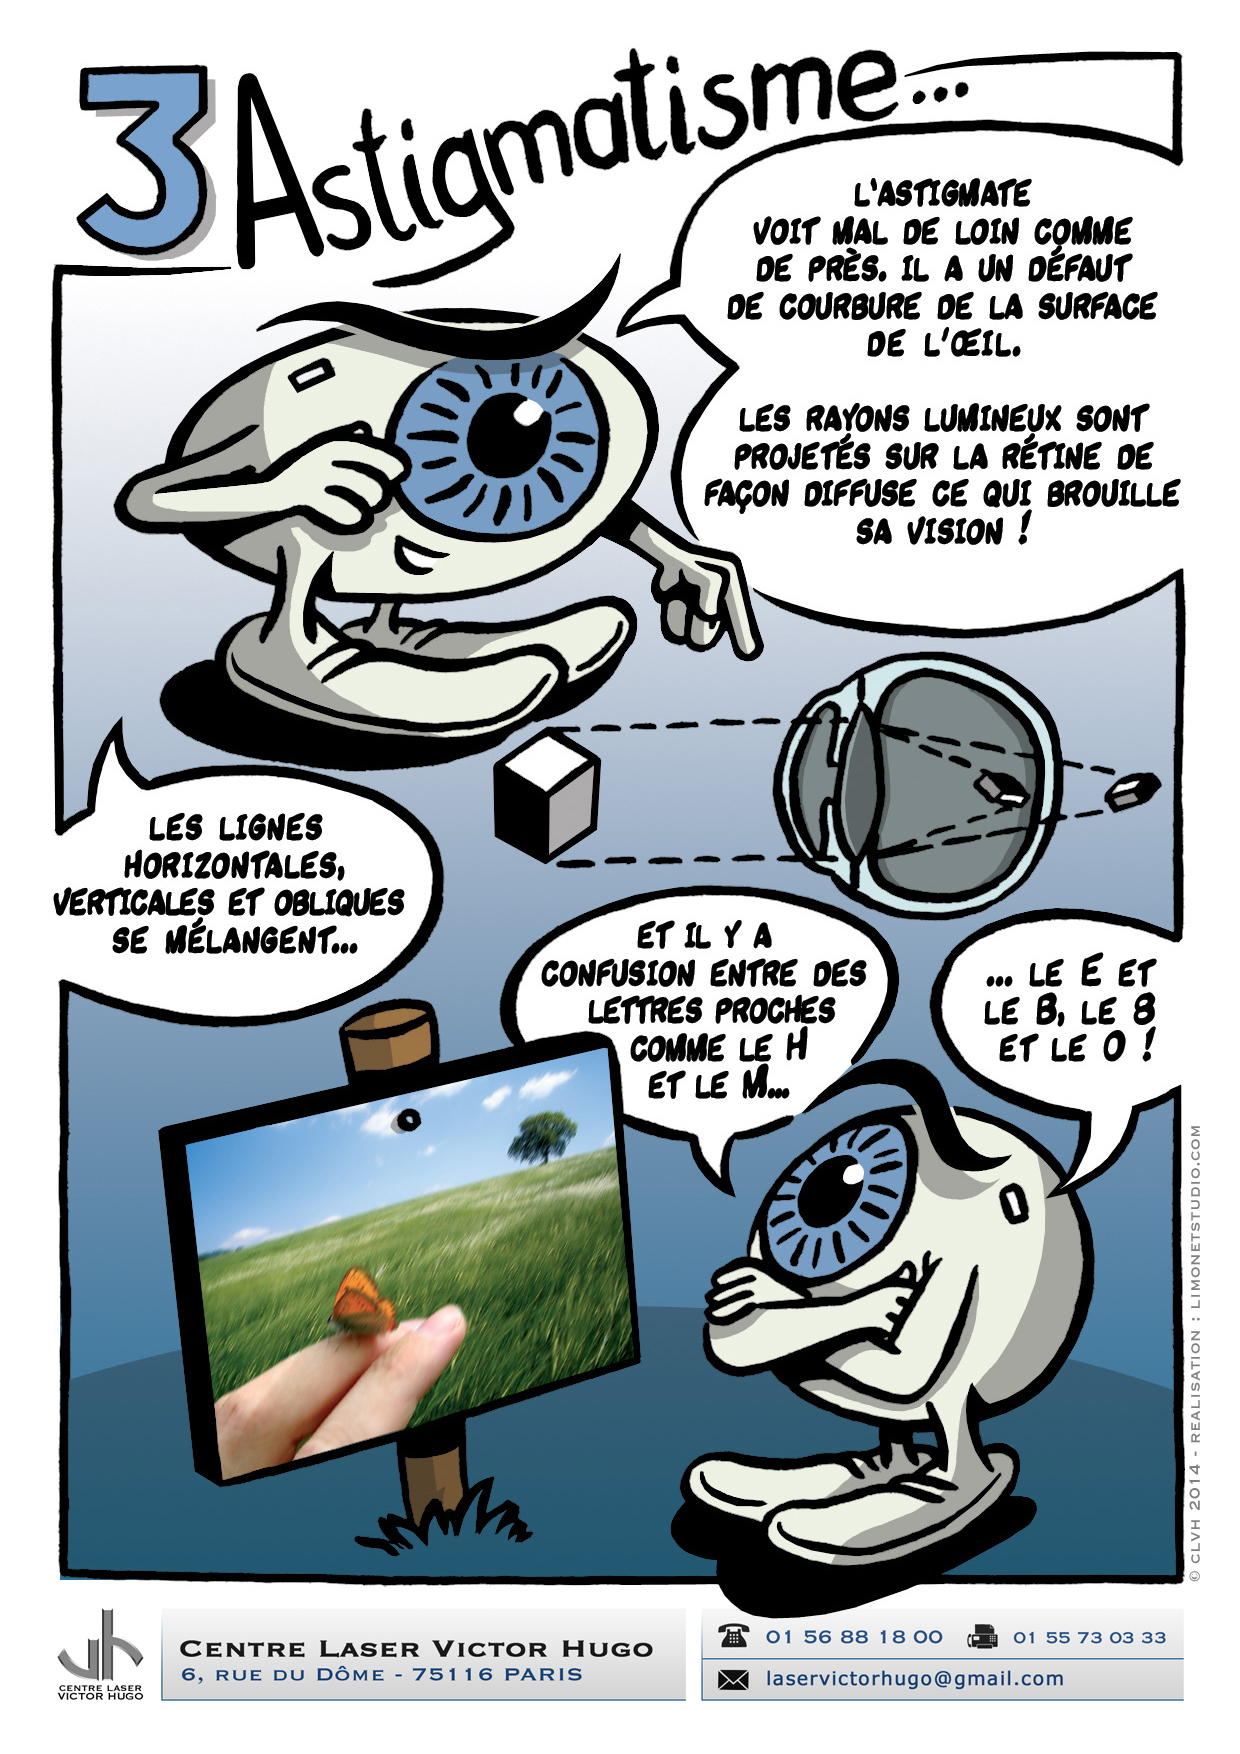

Afin de répondre aux interrogations d'un public de plus en plus intéressé, nous vous proposons cet ouvrage explicatif sous la forme d'une bande dessinée ludique. Cette bédé aborde les troubles de la vision, la chirurgie réfractive (LASIK, PKR et PresbyLASIK), la technique des anneaux et des implants. Cette bébé aborde également l'amblyopie et son traitement orthoptique. Maintenant... à vous de voir !